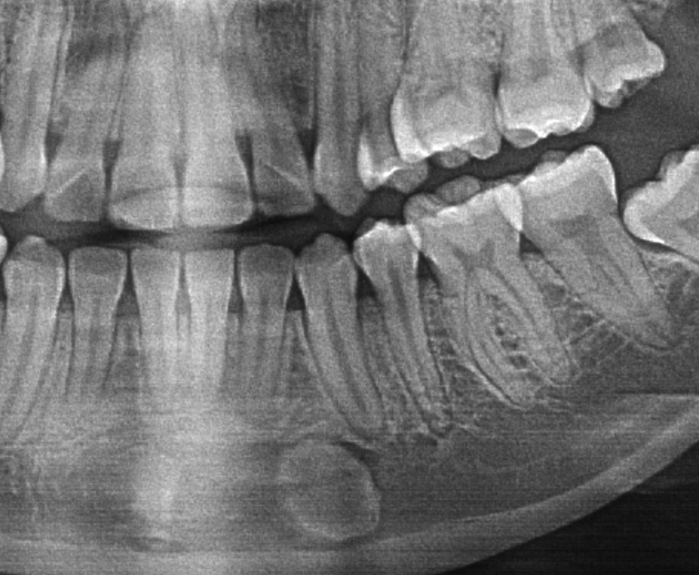

53-year-old man with radiolucency at left mandible

A 53-year-old man with an unusual radiolucency at the inferior border of the left mandible.

27-year-old woman with maxillary lesion

A 27-year-old woman was referred to the oral surgeon by her family dentist due to a radiopaque lesion at the right maxilla between the premolars. …